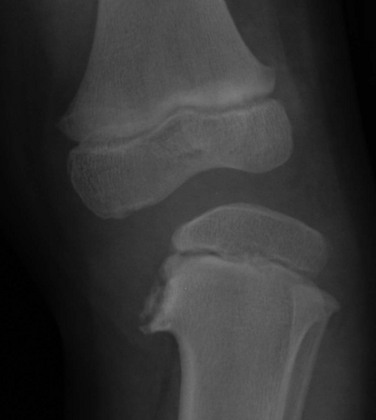

Figure 134-33 Chronic radial head dislocation in a 14-year-old boy with cerebral palsy.

The radial head is displaced posteriorly and has a rounded contour. The radius is bowed anteriorly. Similar findings were present on the opposite side.